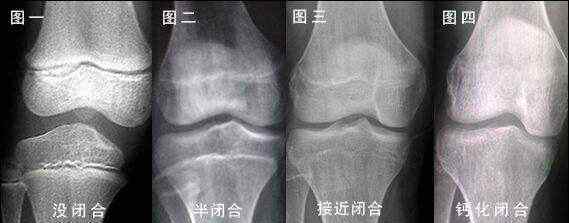

骨骺线闭合是指一根长骨两端的骨骺线消失,实际上意味着它已经失去了自然生长的潜力。

根据我们的传统医学,人的骨骼在男性16-18岁,女性16-20岁时是闭合的。其实这是一种误解。现代医学证明,人的骨骼和脑垂体在20-26岁之间处于半封闭半休眠状态。26岁以后,他们处于完全休眠状态。当然,一些特殊人群的骨骼闭合可以推迟到26岁以后。

所以有需要的人可以先检查一下骨骺线的生长情况。